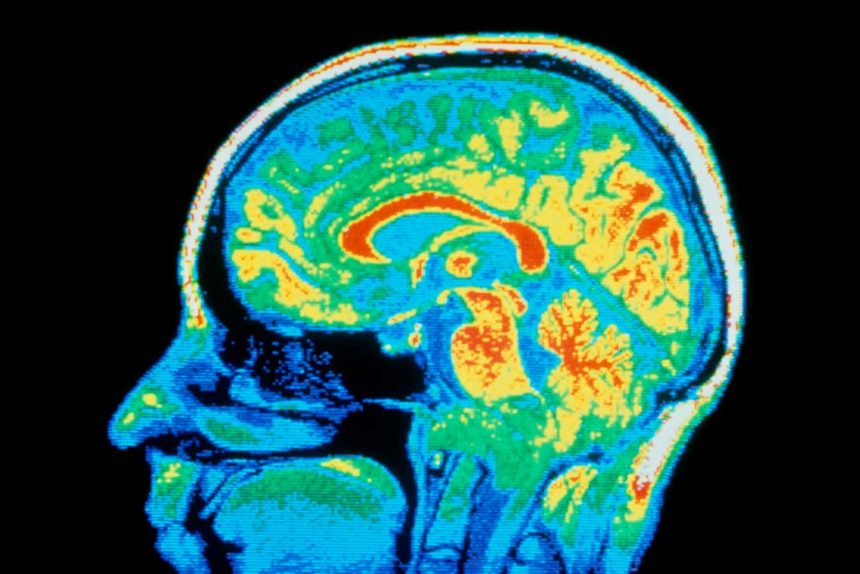

CNRI/SCIENCE PHOTO LIBRARY